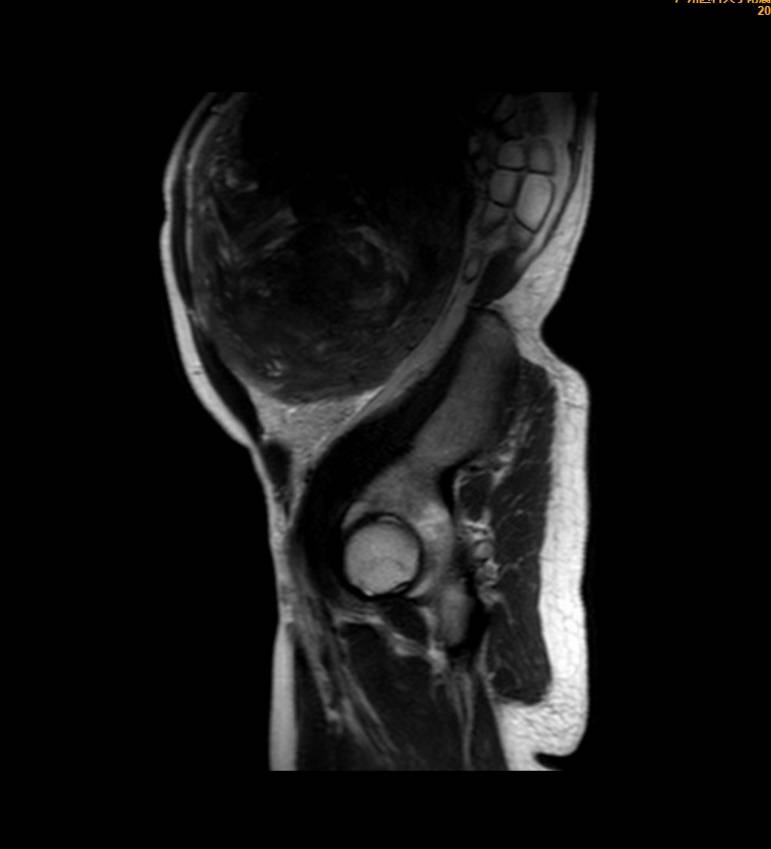

王女士术前影像检查